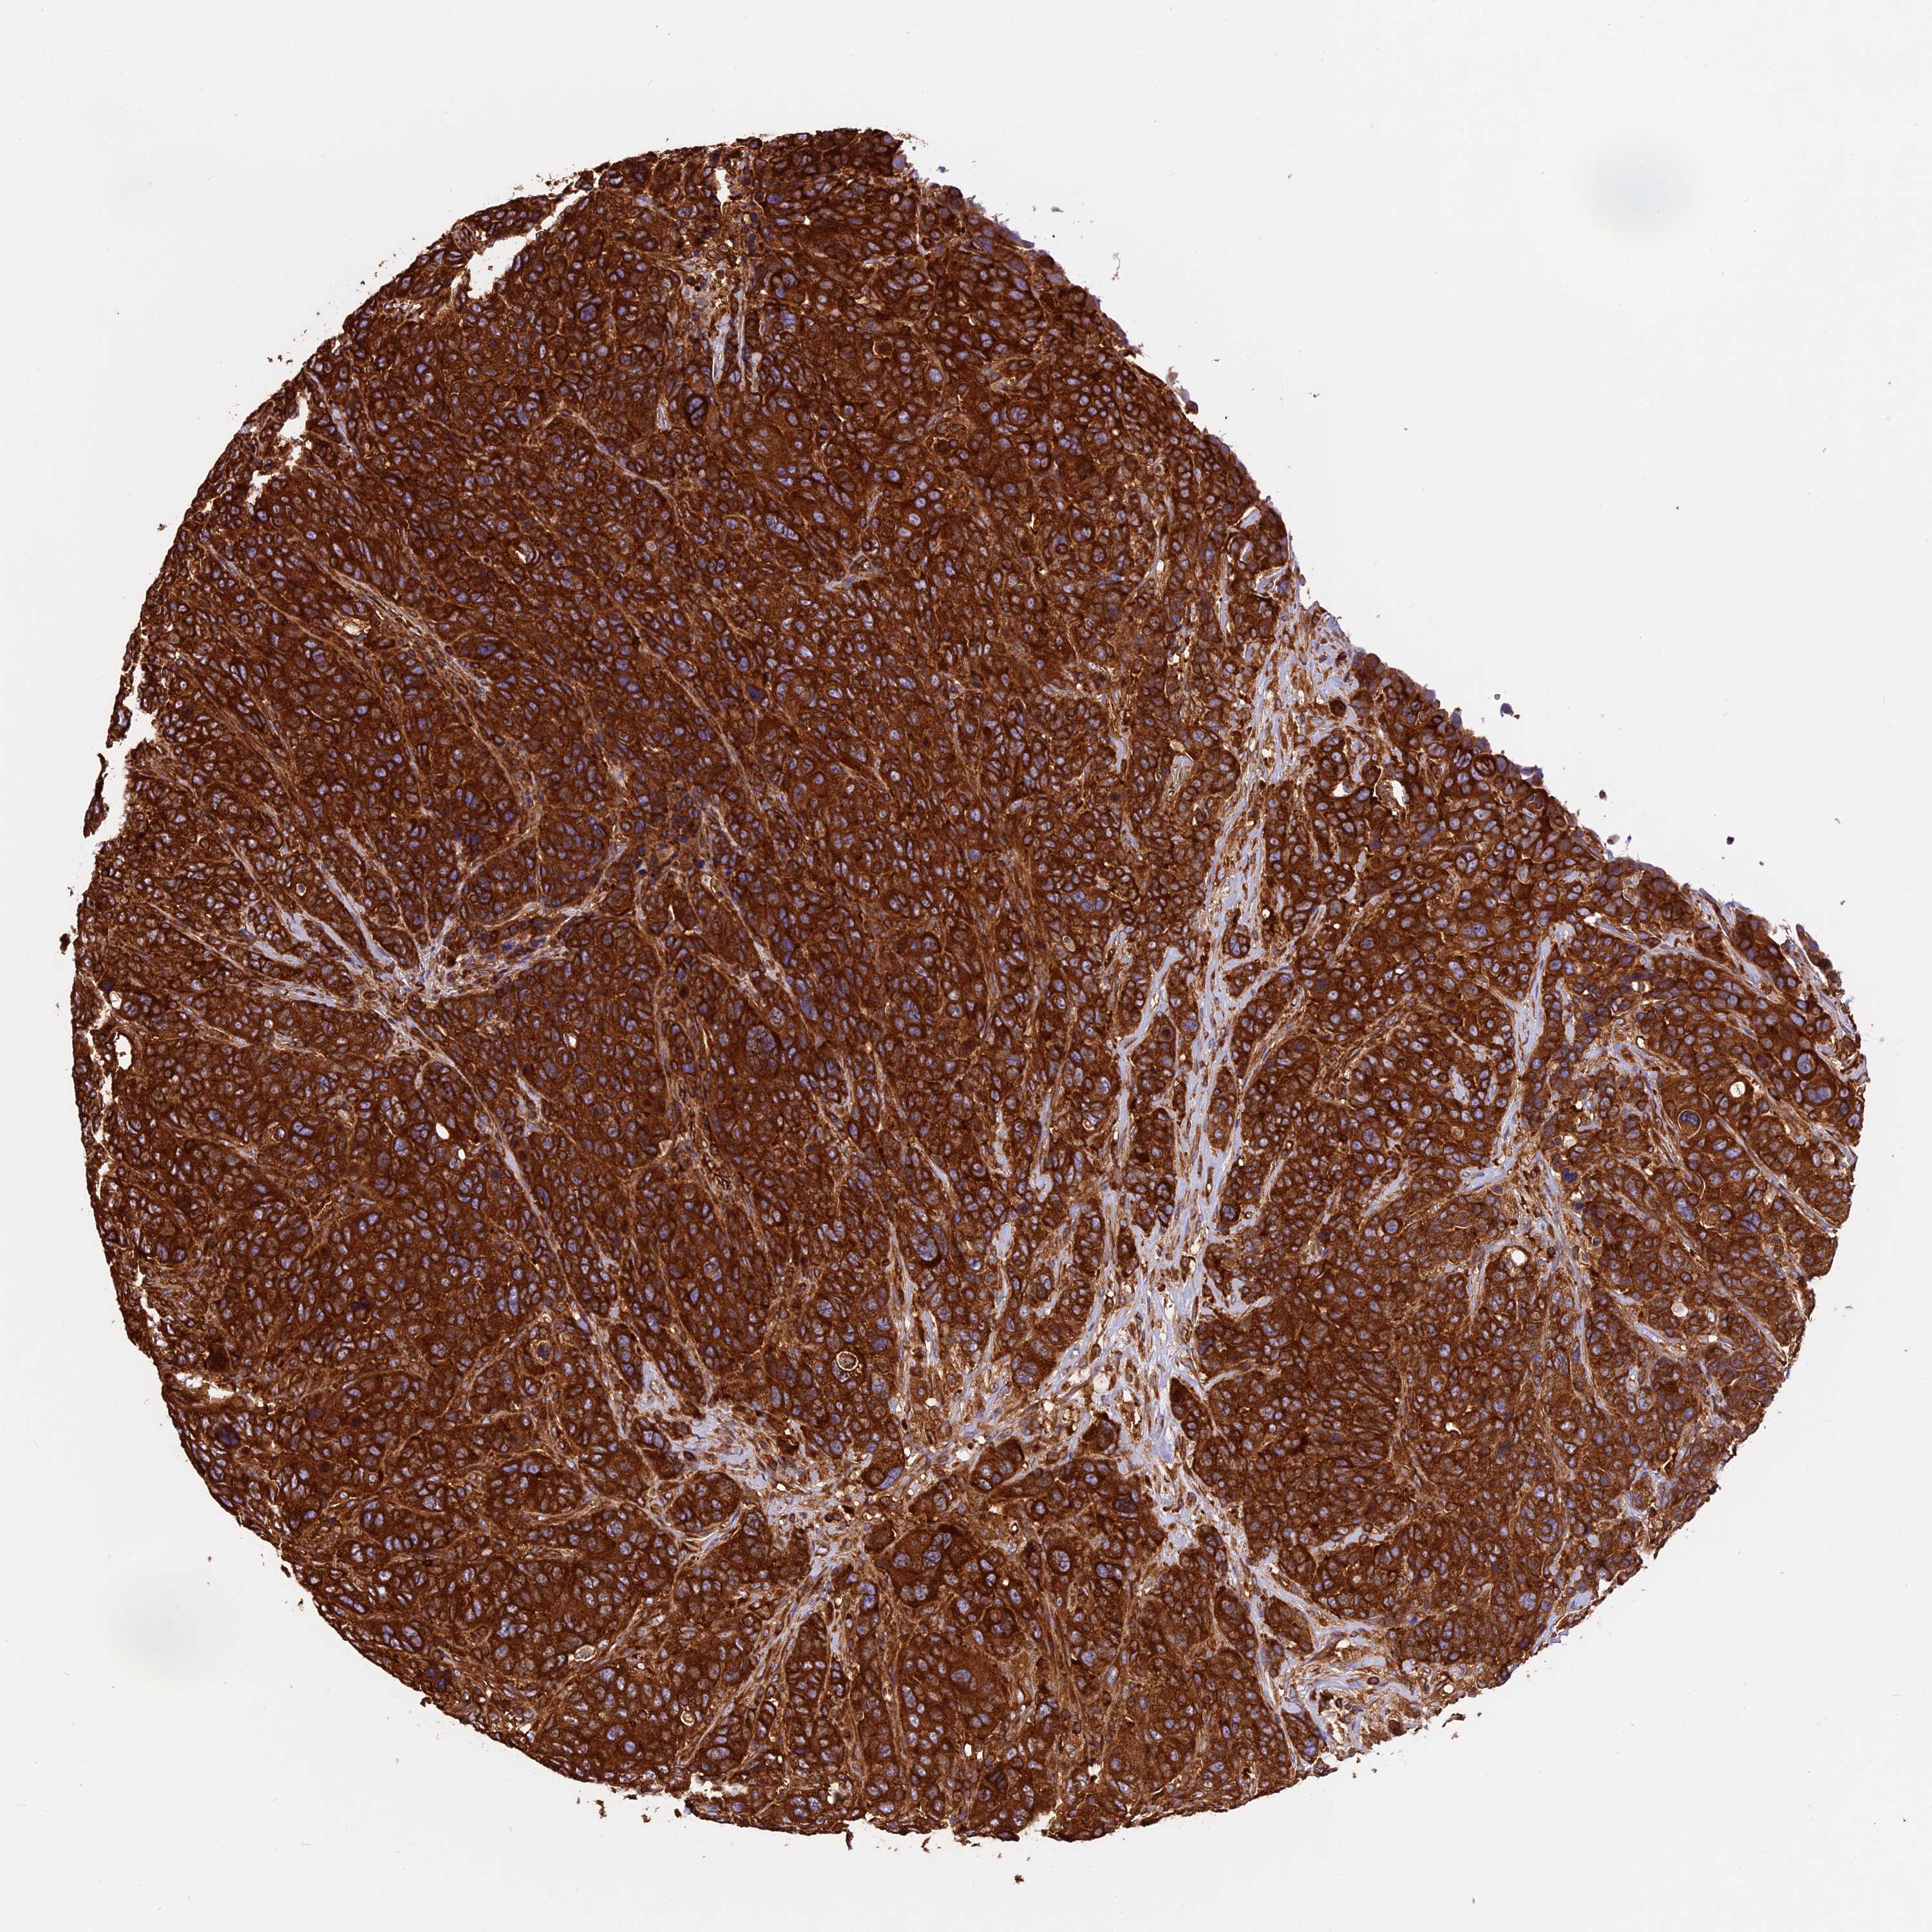

CANCER BREAST CANCER Show tissue menu

BRCA TCGA BRCA VALIDATION PROTEIN EXPRESSION

Breast cancer

Human cancer